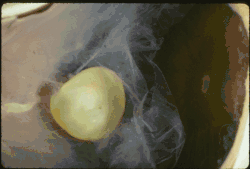

Lens dislocation in Marfan syndrome with the lens being kidney-shaped and resting against the ciliary body

In Marfan syndrome, the health of the eye can be affected in many ways, but the principal change is partial lens dislocation, where the lens is shifted out of its normal position.[17] This occurs because of weakness in the ciliary zonules, the connective tissue strands which suspend the lens within the eye. The mutations responsible for Marfan syndrome weaken the zonules and cause them to stretch. The inferior zonules are most frequently stretched resulting in the lens shifting upwards and outwards, but it can shift in other directions as well. Nearsightedness (myopia), and blurred vision are common due to connective tissue defects in the eye.[18] Farsightedness can also result particularly if the lens is highly subluxated. Subluxation (partial dislocation) of the lens can be detected clinically in about 60% of people with Marfan syndrome by the use of a slit-lamp biomicroscope.[18] If the lens subluxation is subtle, then imaging with high-resolution ultrasound biomicroscopy might be used.[19]